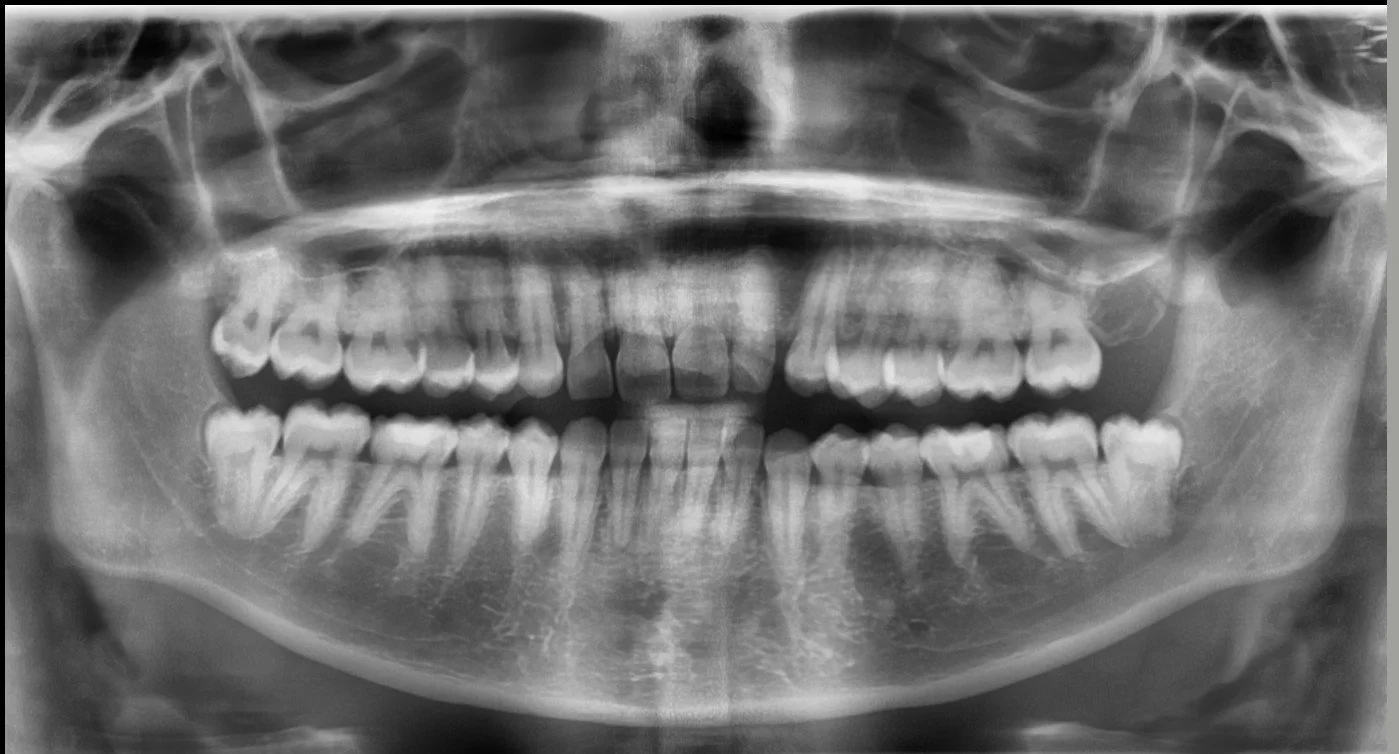

Your Jaw Has a Superpower.

It’s pretty wild, but your jaw can clamp down with over 200 pounds of pressure on your back molars. Think about that for a second — that's the same pressure as a car tire, all concentrated on a tiny surface!

When your teeth are perfectly aligned, that superpower is amazing. It's distributed evenly, letting you chew through anything from a crunchy apple to a steak. All your teeth work together as a team, sharing the load.

When your teeth don't line up correctly, that 200-pound force goes rogue. Instead of a balanced team, you get a few overworked teeth taking all the punishment. This is where the real damage starts.